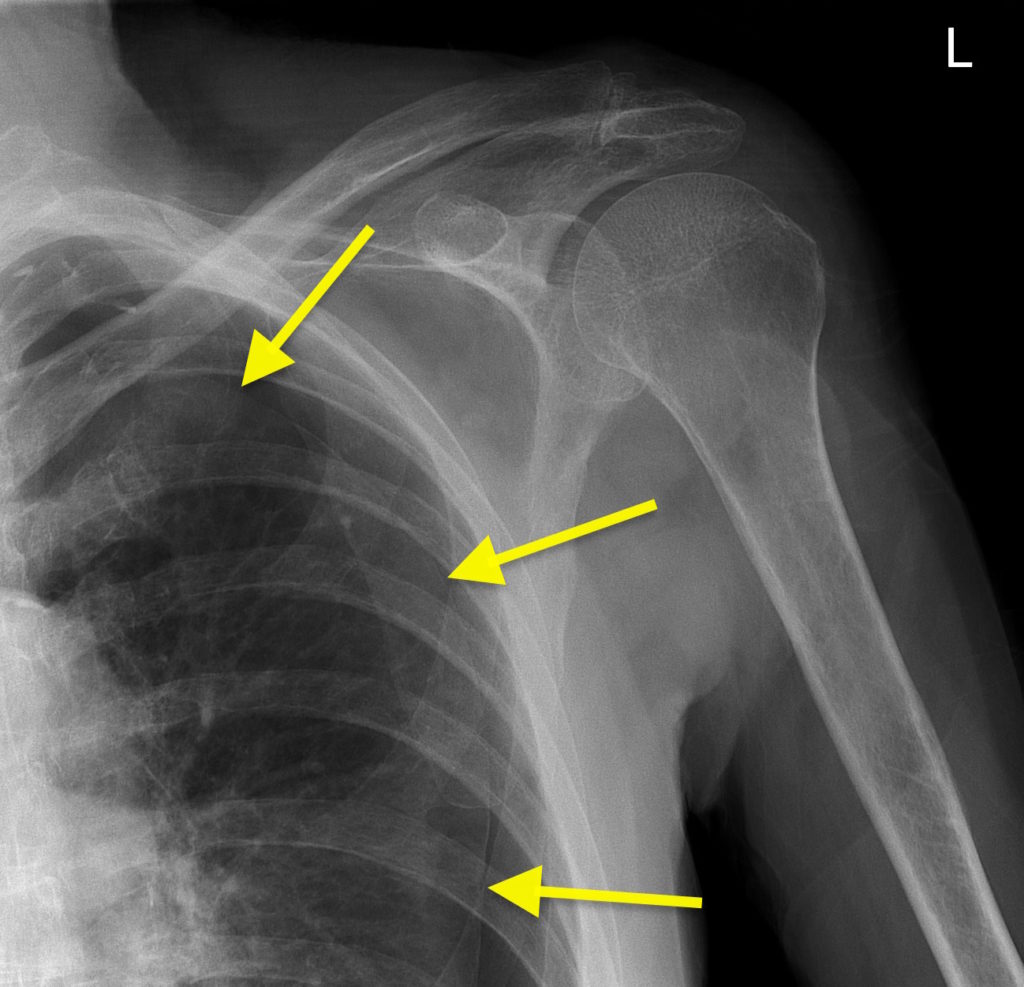

Pneumothorax on shoulder X-ray – Radiology at St. Vincent’s University …

“There’s something in your lung”: five years ago today